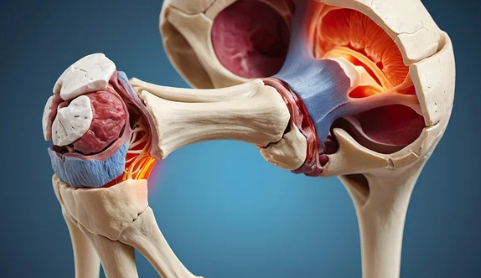

고관절 탈구는 엉덩이뼈(골반)와 허벅지뼈(대퇴골)가 연결된 관절에서 대퇴골두가 제자리에서 이탈하는 상태를 의미합니다. 이는 보통 강한 외부 충격이나 관절의 퇴행성 변화로 인해 발생합니다.

고관절이 탈구되면 즉각적인 통증과 보행 장애가 발생합니다.

- 엉덩이 및 사타구니 부위 극심한 통증 (움직일 때 심해짐)

- 다리의 길이 차이 발생 (탈구된 쪽이 짧아짐)

- 다리 모양의 비정상적인 변형 (내회전 또는 외회전)